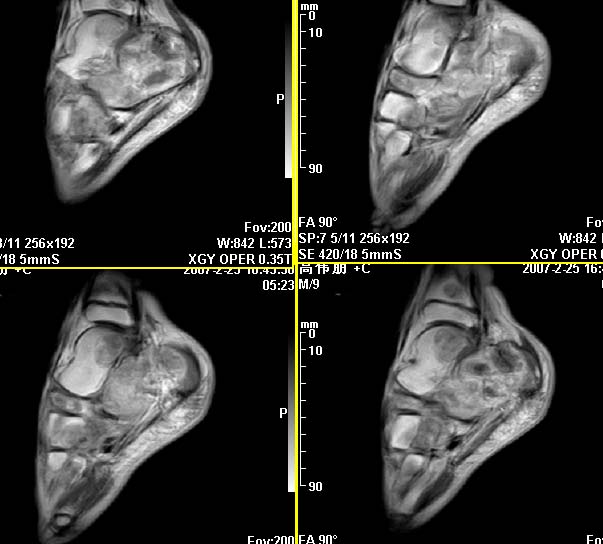

m,9y,左足肿痛半年,无皮肤发红,诱因为外伤后起因。无发烧,无其他疾病。临床考虑多发血管瘤。mri增强后有强化,请分析。是骨髓瘤吗?

左足多发囊状膨胀性骨质破坏,边较清,关节间隙及软组织未见明显异常。结合临床。可排除炎症性病变。病变中心为骨髓腔。有强化。中心坏死。嗜酸性肉芽肿可能大。

多发内生性软骨瘤

结合临床考虑血管瘤侵犯左足骨质。

今天从天津肿瘤医院传来消息:病理结果是非骨化性纤维瘤。